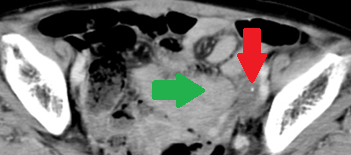

Red arrows — transition point. Multiple air-fluid levels (Courtesy Dr. V. Penopoulos)